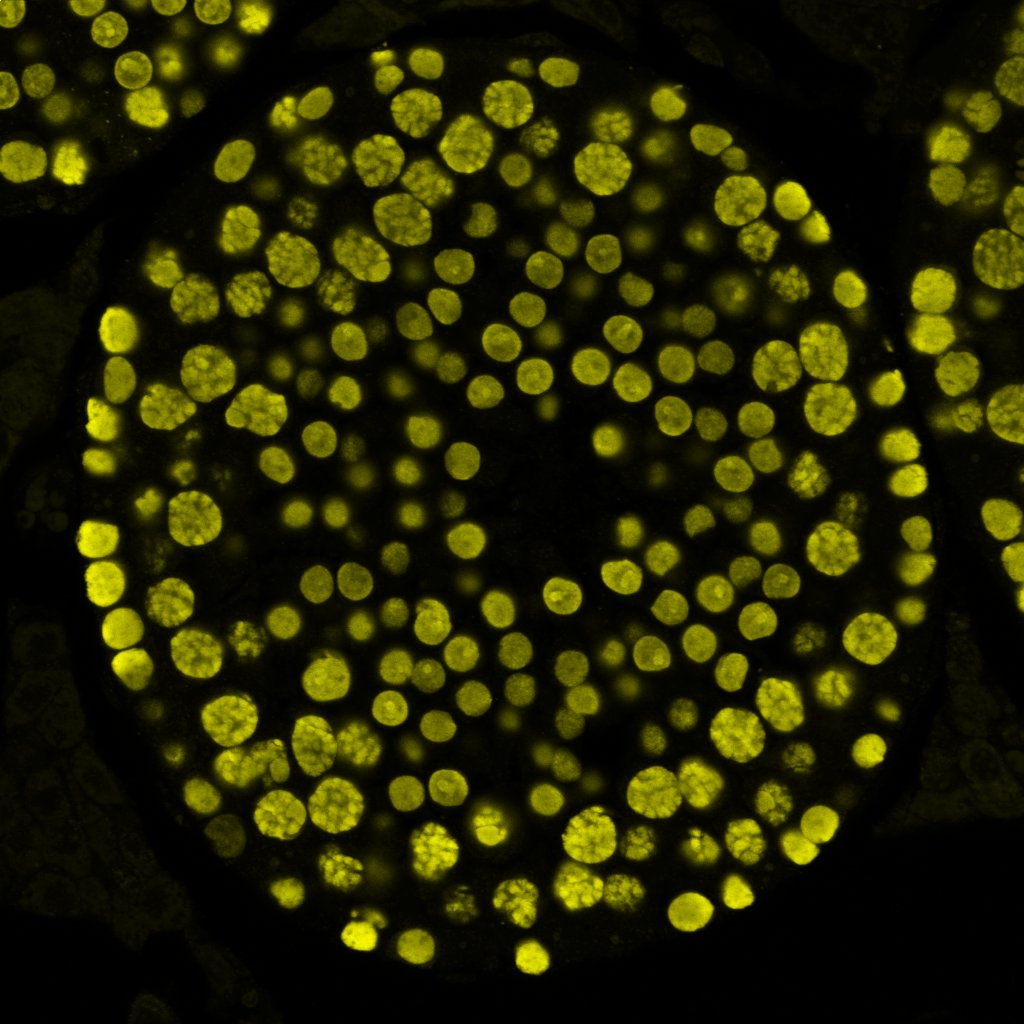

Dr Giulia Silvani

• Microscope: Olympus FV4000

This image captures brain cancer cells (glioblastoma, inner circle) breaking through the wall of a tiny artificial blood vessel (outer circular structure), recreated on a microfluidic chip, a miniature “lab-on-a-chip" that mimics how blood flows in the body. By watching how these cells invade the vessel under realistic, flowing conditions, researchers can better understand how aggressive cancers spread and test new ways to stop them, without the need for animal models.